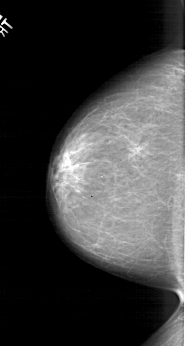

LEFT_CC LINES 5881 PIXELS_PER_LINE 3181 BITS_PER_PIXEL 12 RESOLUTION 43.5 NON_OVERLAY